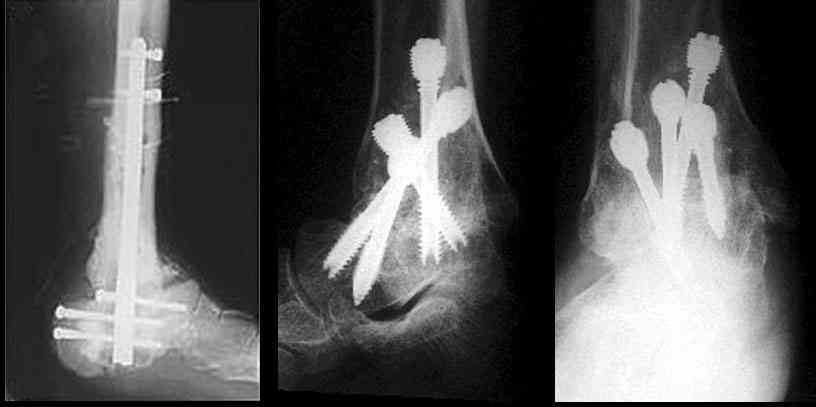

Можно: 65-летняя пациентка, оперирована по поводу несросшегося в гипсе перелома лодыжек с патологической вальгусной установкой стопы и выраженным нарушением опрной функции. Оперирована через 6 месяцев после травмы. Рентгенограммы через 4 месяца после операции.

Существуют специальные системы для артродеза голеностопного сустава. См. приложение

Уважаемый А.Семенистый. Складывается впечатление, что вы выполнили трехсуставный артродез, уж больно длинные блокирующие винты. Не мешают ли они пациентке при ходьбе?

Да конечно винты длинноваты! Мешают ли ходить? Во всяком случае субьективно пациентка удовлетворена. Ходит, естевственно, хуже чеи до травмы, но намного лучше, чем до операции.